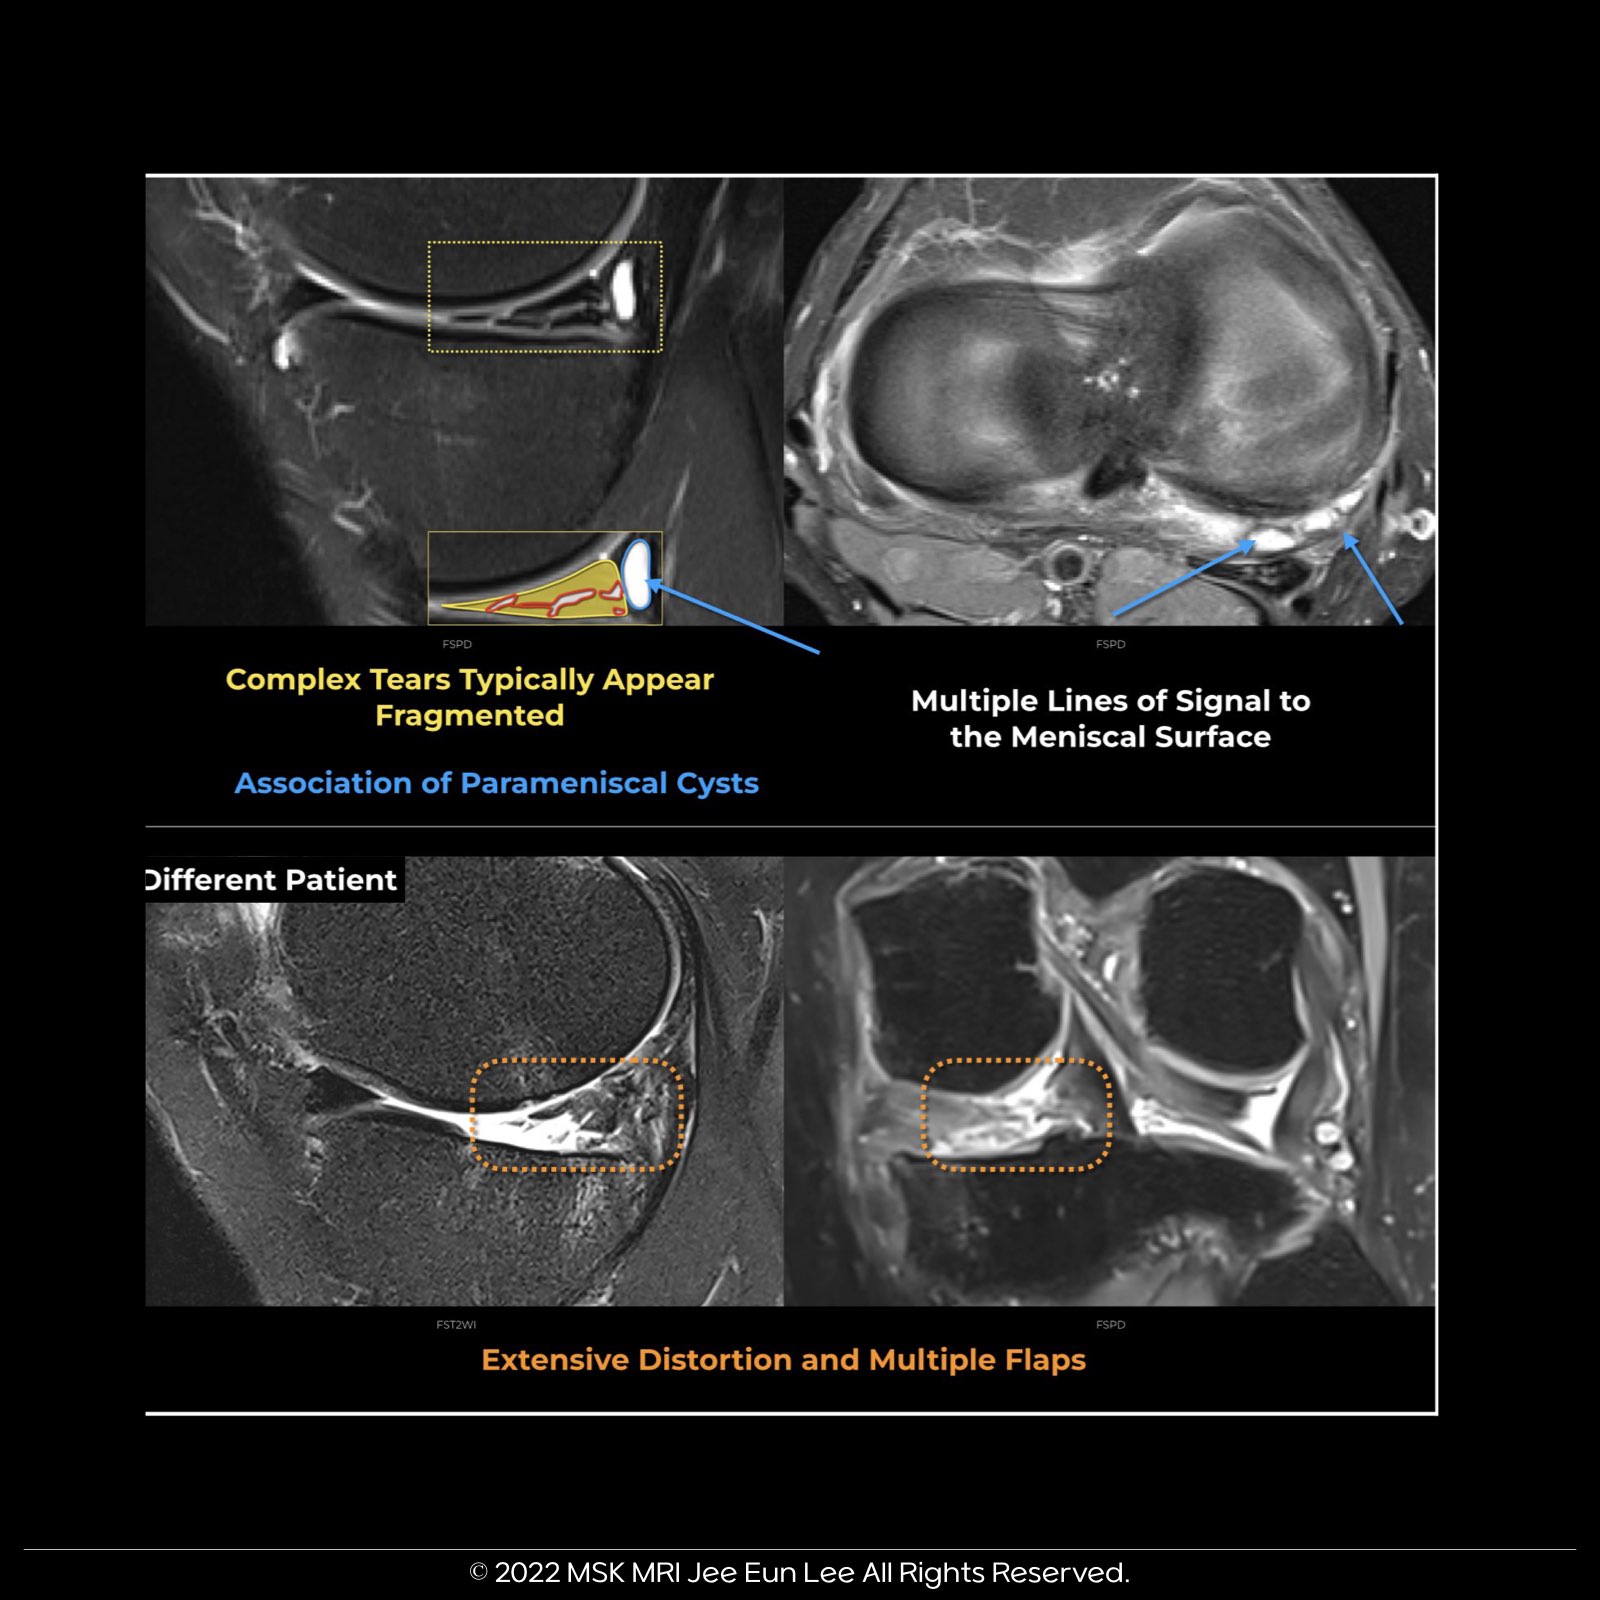

๐ Understanding Complex Meniscal Tears

- A combination of radial, horizontal, and longitudinal components.

- Extends on multiple planes, possibly forming separate flaps.

- ๐ธ On MRI: Look for vertical & horizontal patterns, hinting at a fragmented structure.

๐จ 'Complex Tear': Indicates extensive distortion & multiple signal lines to the surface. Predicts multiple flaps during arthroscopy.